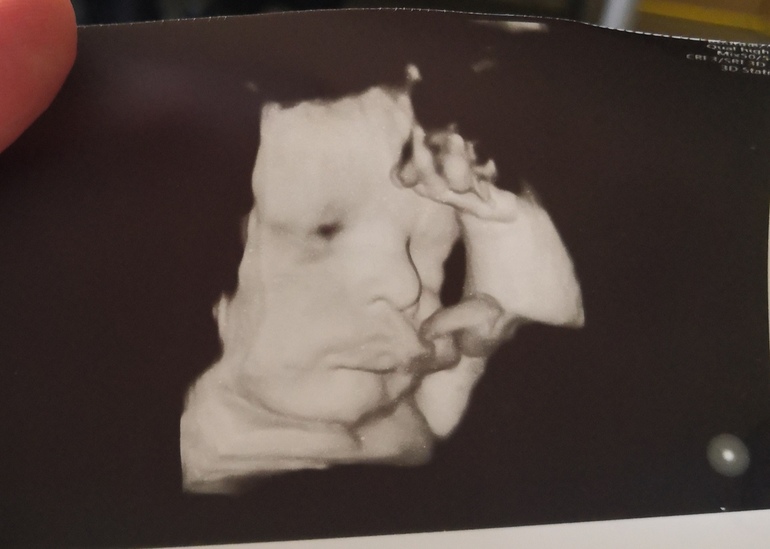

Ну и мой сладенький. Узистка сказала при многоводии фотки хорошие, но мой стесняшка всё также не любит фоткаться, закрывается ручками или корчит моськи😍🤗